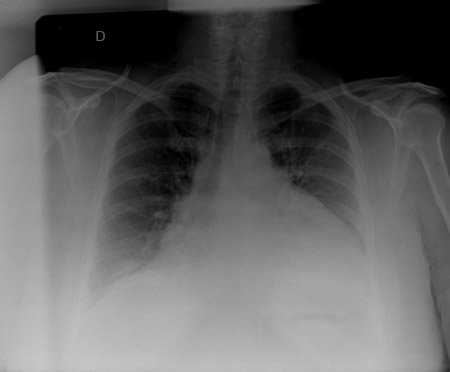

Radiografía de tórax

Una radiografía de tórax puede mostrar una silueta cardíaca en forma de botella de agua con una franja de grasa pericárdica distintiva, lo que sugiere un derrame pericárdico extenso. También puede haber presencia de derrames pleurales.[Figure caption and citation for the preceding image starts]: El RT en un paciente con un derrame pericárdico que muestra hallazgos típicos de una silueta cardíaca en forma botella de agua con una raya de grasa pericárdica gruesa y diferenciada.De la colección del Dr. Rajdeep Khattar [Citation ends].